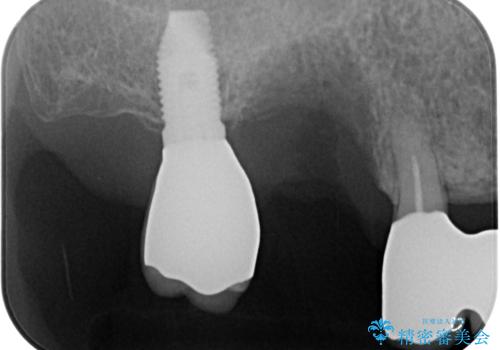

抜けてしまった奥歯 短期間インプラント治療

- インプラントが脱落してしまったとのことで来院された患者様です。

歯肉は綺麗に治癒しており、インプラント埋入に十分な骨があったため、速やかにインプラント埋入を行うこととしました。

インプラント埋入の状態が良ければ即日で仮歯を装着し、十分な生着が確認され次第、オールセラミッククラウンにて補綴治療を行うこととしました。

インプラントの初期固定も埋入後の生着もスムーズであったので、埋入から3ヶ月で無事に治療を終えることができました。